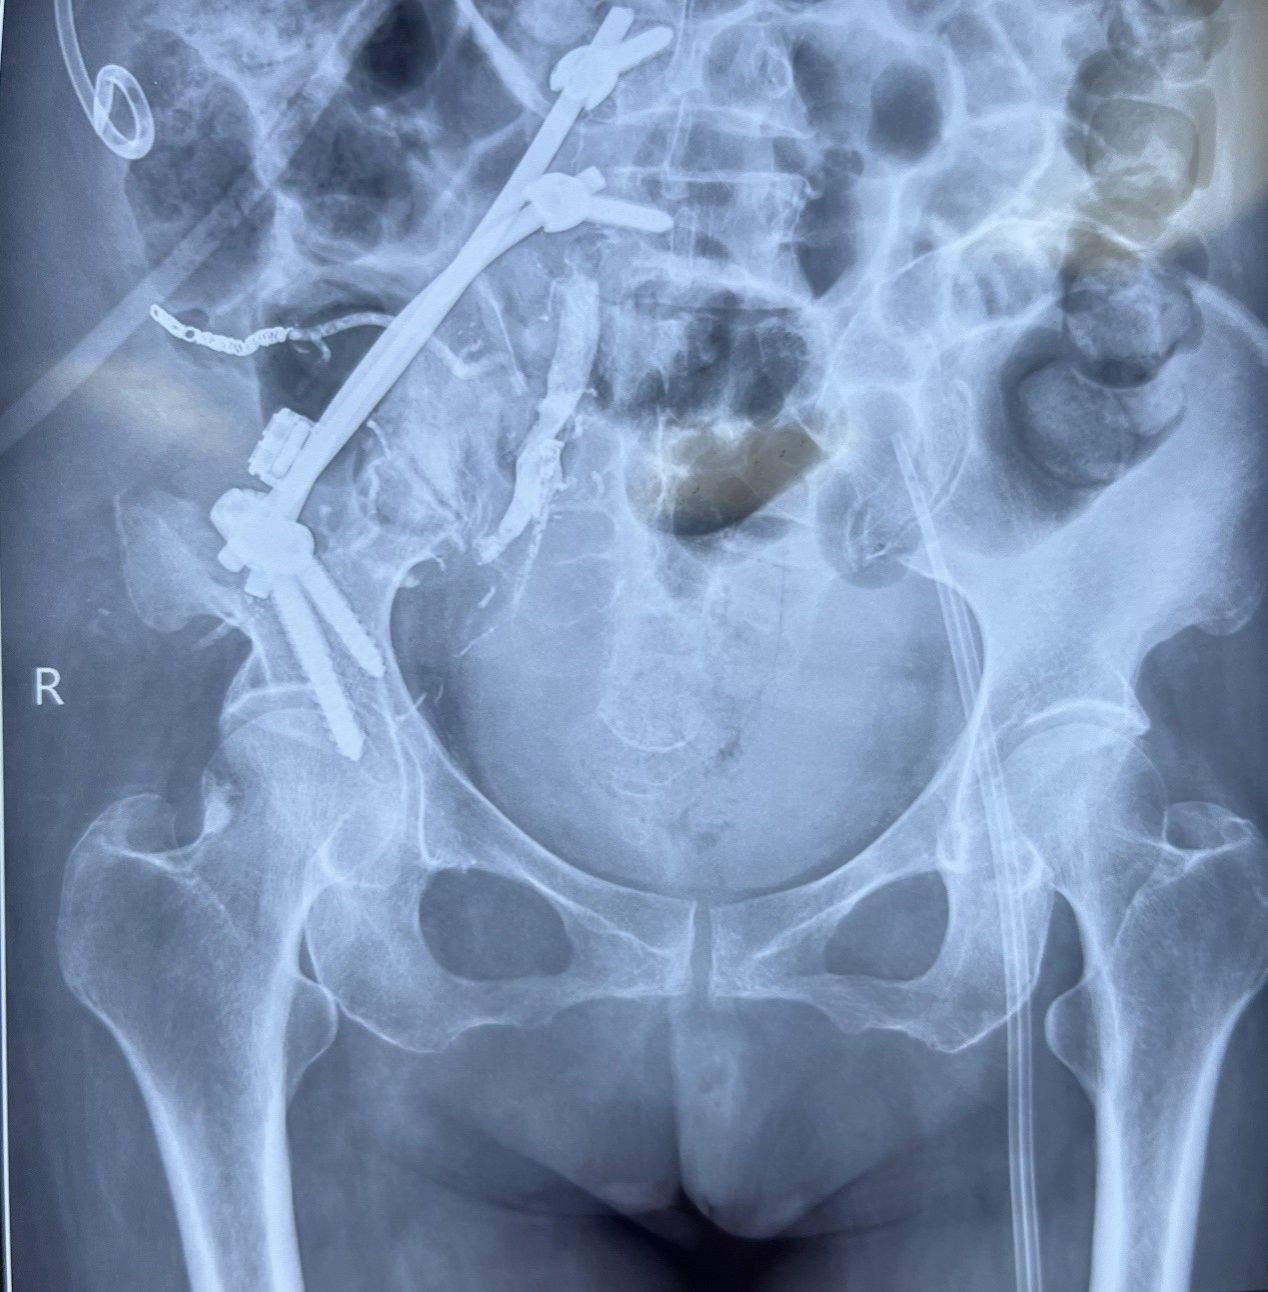

手术当日,在首席专家骨科主任医师王栋教授的统筹指挥下,多学科专家紧密协作,血管外科专家首先经介入栓塞了肿瘤供血血管降低术中出血;骨科团队王国毓教授治疗组则在神经监测仪的实时保护下,小心翼翼地分离被肿瘤侵犯的血管神经丛,最终将这一巨大瘤体连同受侵的骶骨、髂骨完整移除。随后,团队利用脊柱骨盆钉棒系统成功重建了骨盆环的稳定性。手术全程出血量得到有效控制,患者生命体征平稳。

术后患者恢复良好,在重症监护团队精心管理下平稳度过危险期,目前正在积极康复中,疼痛症状显著缓解,生活质量得到极大改善。术后病理确诊为甲状腺转移瘤,为后续继续行碘131治疗提供了明确方向。